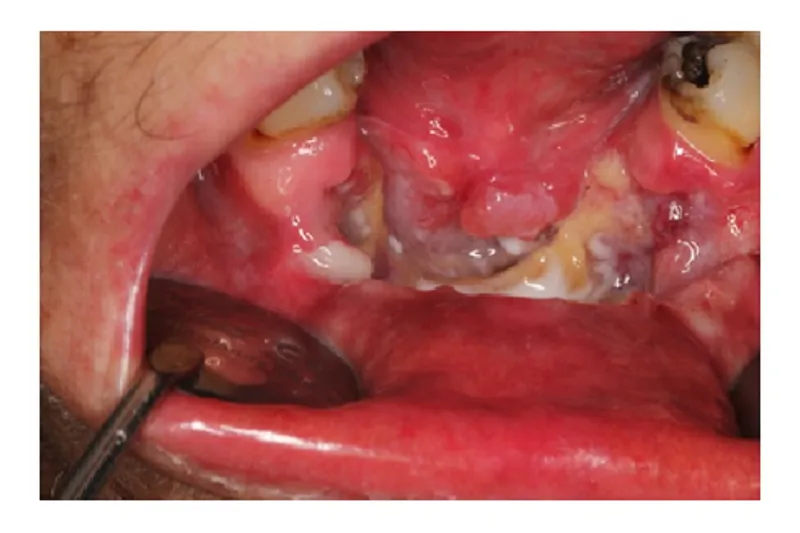

BAGGRUND – Planocellulært karcinom udgået fra mundhulens overfladeepitel er den hyppigste (> 90 %) form for oral cancer. De kliniske tegn på planocellulært karcinom er typisk et ikke-helende sår med voldformede rande og induration. Der kan dog også forekomme røde og hvide samt nodulære forandringer uden ulceration.

PATIENTTILFÆLDE – En 55-årig kvinde blev henvist til Kæbekirurgisk afdeling, Sydvestjysk Sygehus Esbjerg, med henblik på diagnostik og behandling af en nekrotisk knogledefekt i underkæben efter i en periode at være blevet behandlet kirurgisk i privat praksis. Klinisk sås en stor ulceration med voldformede rande og stor destruktion af processus alveolaris. CBCT viste stor destruktion af den faciale knogle i underkæbefronten. Patienten blev henvist til Øre-næse-hals-afdelingen pga. mistanke om planocellulært karcinom. Patienten kom herefter i kræftpakkeforløb, hvor diagnosen blev bekræftet ved biopsi. En primær resektion blev fulgt op af stråle- og kemoterapi. Fem måneder postoperativt blev der konstateret recidiv ekstraoralt på hagen, som blev behandlet med palliativ kemoterapi.